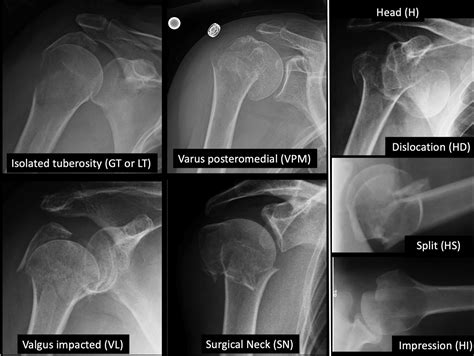

Classification of Proximal Humerus Fractures

Proximal humerus fractures are classified based on the location and pattern of the fracture. The most common classification systems include:

• Neer Classification: This system categorizes fractures based on the number of parts involved (one, two, three, or four parts).

• AO/OTA Classification: This system uses a more detailed coding system to describe the fracture pattern and severity.

Understanding the classification of the fracture helps healthcare providers determine the appropriate treatment plan.

A proximal humerus fracture occurs at the top of the humerus, the long bone in the upper arm. This type of fracture is often the result of a fall onto an outstretched hand or a direct blow to the shoulder. The proximal humerus is composed of several parts, including the head, greater tuberosity, lesser tuberosity, and the surgical neck. Fractures can occur in any of these areas, and the severity can vary from minor cracks to complete breaks.